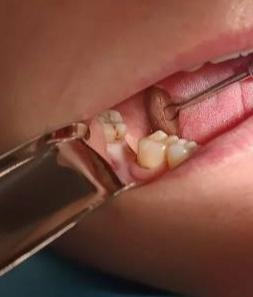

На начальном фото — классическая картина: моляр, от которого остался только корень. Стенок нет, жевать нечем, стандартная рекомендация — удалять и ставить имплант. Но корни были живыми, крепкими, и я решил побороться.

В корневые каналы установили анкерный штифт — металлический каркас, который взял на себя нагрузку. Вокруг штифтов послойно восстановили коронковую часть современным композитом. Никаких коронок, никаких мостов, только свой корень и мои руки.

На фото «После» — зуб, который обречённо торчал из десны, снова в строю. Он жуёт, он живёт, он свой. Анкер — это не страшно, если знаешь, куда и зачем его ставить.